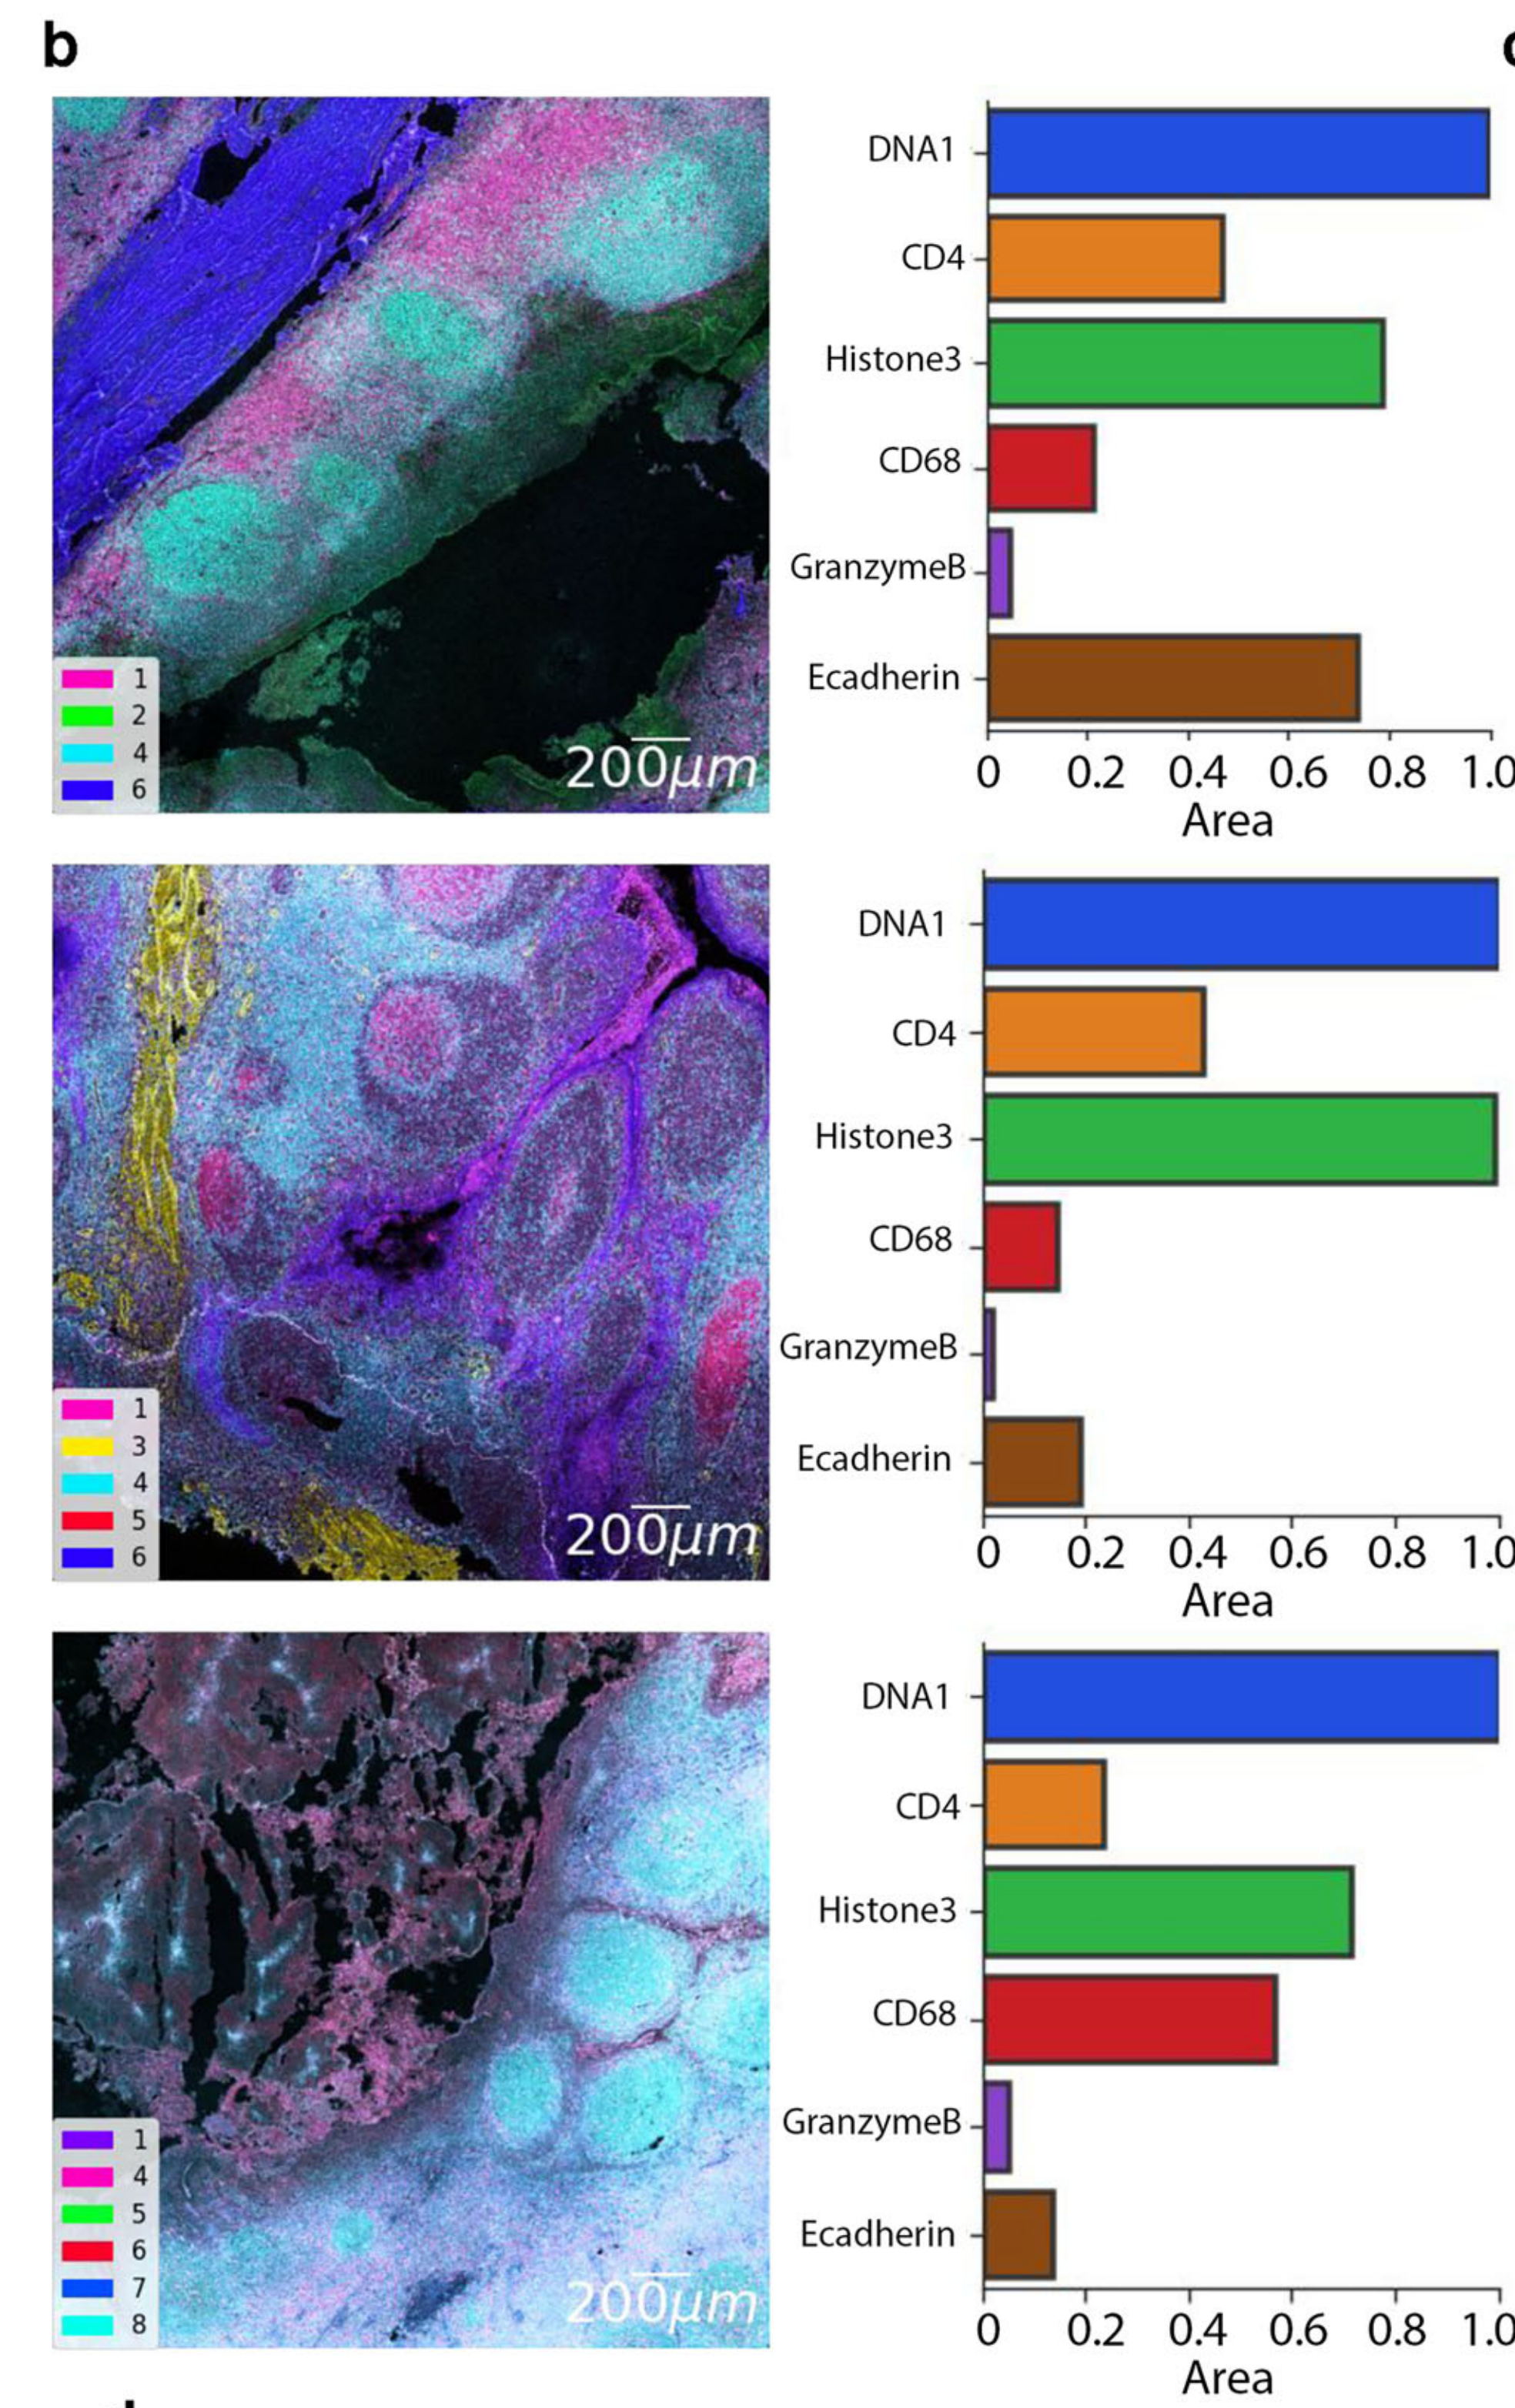

Allam et al., 2021

Spatially visualized single-cell pathology of highly multiplexed protein profiles in health and disease